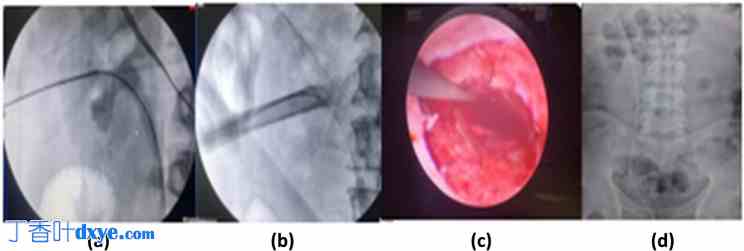

所有患者均接受了非增强CT检查以评估肾结石。在完成所有必要的实验室和影像学检查后,进行了麻醉前评估。在向患者及其近亲解释了手术步骤、预期结果以及数据用于研究目的后,获得了他们的书面知情同意。所有患者在进入手术室前均接受了单剂量术前抗生素预防(根据医院最佳实践指南),即静脉注射头孢曲松(1 g)和/或阿米卡星(500 mg)。患者在接受脊髓麻醉或全身麻醉后,均保持截石位。不适合脊髓麻醉或脊髓麻醉失败的患者则采用全身麻醉。在膀胱镜引导下,置入5 Fr输尿管导管,进行同侧逆行肾盂造影,以辅助在透视下进行肾穿刺。随后,患者被重新置于俯卧位,并垫上足够的凝胶垫,两侧腰部下方平行放置两个垫枕。在透视引导下,使用18号金刚石尖端穿刺针进行肾穿刺。使用Blueneem® Amplatz肾扩张套装,在0.038英寸Terumo导丝的引导下,对肾动脉通道进行连续扩张,建立肾动脉通路。采用12Fr硬性肾镜(Richard Wolf® GmbH,德国克尼特林根)和气压碎石机(Swiss Lithoclast® Master)进行经皮肾镜取石术(TTmPCNL)。术中采用重力或灌注泵注入生理盐水,以获得清晰的内镜视野。使用取石钳和伯努利手法取出结石碎片。术中通过内镜直视和透视确保结石完全清除。经皮肾镜取石术(TTmPCNL)无需放置肾造瘘管和双J管(完全无管),确保无残余结石、活动性出血、造影剂外渗和肾盂肾盏损伤(图1)。所有患者术中均接受单剂量氨甲环酸(1克)和静脉注射袢利尿剂(呋塞米20毫克)。输尿管导管置于Foley导尿管内,并放置于尿袋中。术后第一天或患者出院前拔除输尿管导管和Foley导尿管。

图 1.

手术步骤(经皮肾镜取石术):a. 导丝置于上段输尿管内,进行肾盏穿刺;b. 体外冲击波碎石后,在 Amplatz 鞘管内清除结石;c. 导丝仍置于鞘管内时,在取出 Amplatz 鞘管前检查通道;d. 留置输尿管导管后出院。